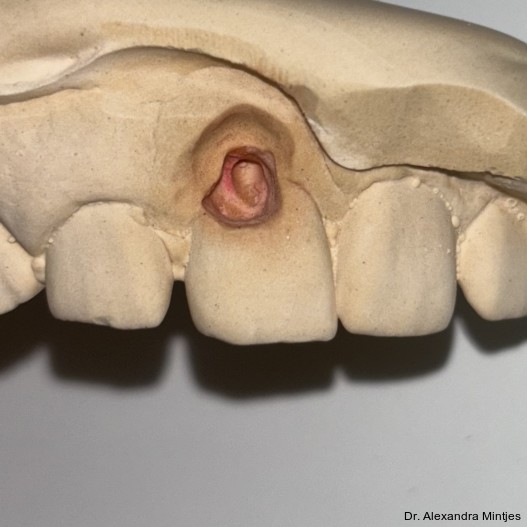

Die Kavität wurde durch einen digitalen Scan abgeformt. Zusätzlich wurde eine Doppelmischabformung unter Verwendung von Alginat und Systoloid®-Hydrokolloid angefertigt, um eine spätere Anpassung der Restauration auf dem Gipsmodell durch die Zahntechnikerin zu ermöglichen (Abb. 5). Dabei spielte insbesondere der subgingivale Anteil eine entscheidende Rolle, da eine Anpassung in diesem Bereich direkt am Patienten eine erhebliche klinische Herausforderung darstellen würde. Danach wurde ein Schaumstoffpellet als temporärer Verschluss in die Kavität eingebracht, bevor ein provisorisches Onlay aus Telio® (Ivoclar) angefertigt wurde. Somit konnte eine retentive Formgebung und ein damit verbundenes Frakturrisiko bei der folgenden Entfernung des Provisoriums vermieden werden. Die Oberfläche des Provisoriums wurde bewusst rau gelassen, um eine möglichst einfache Entfernung zu gewährleisten.